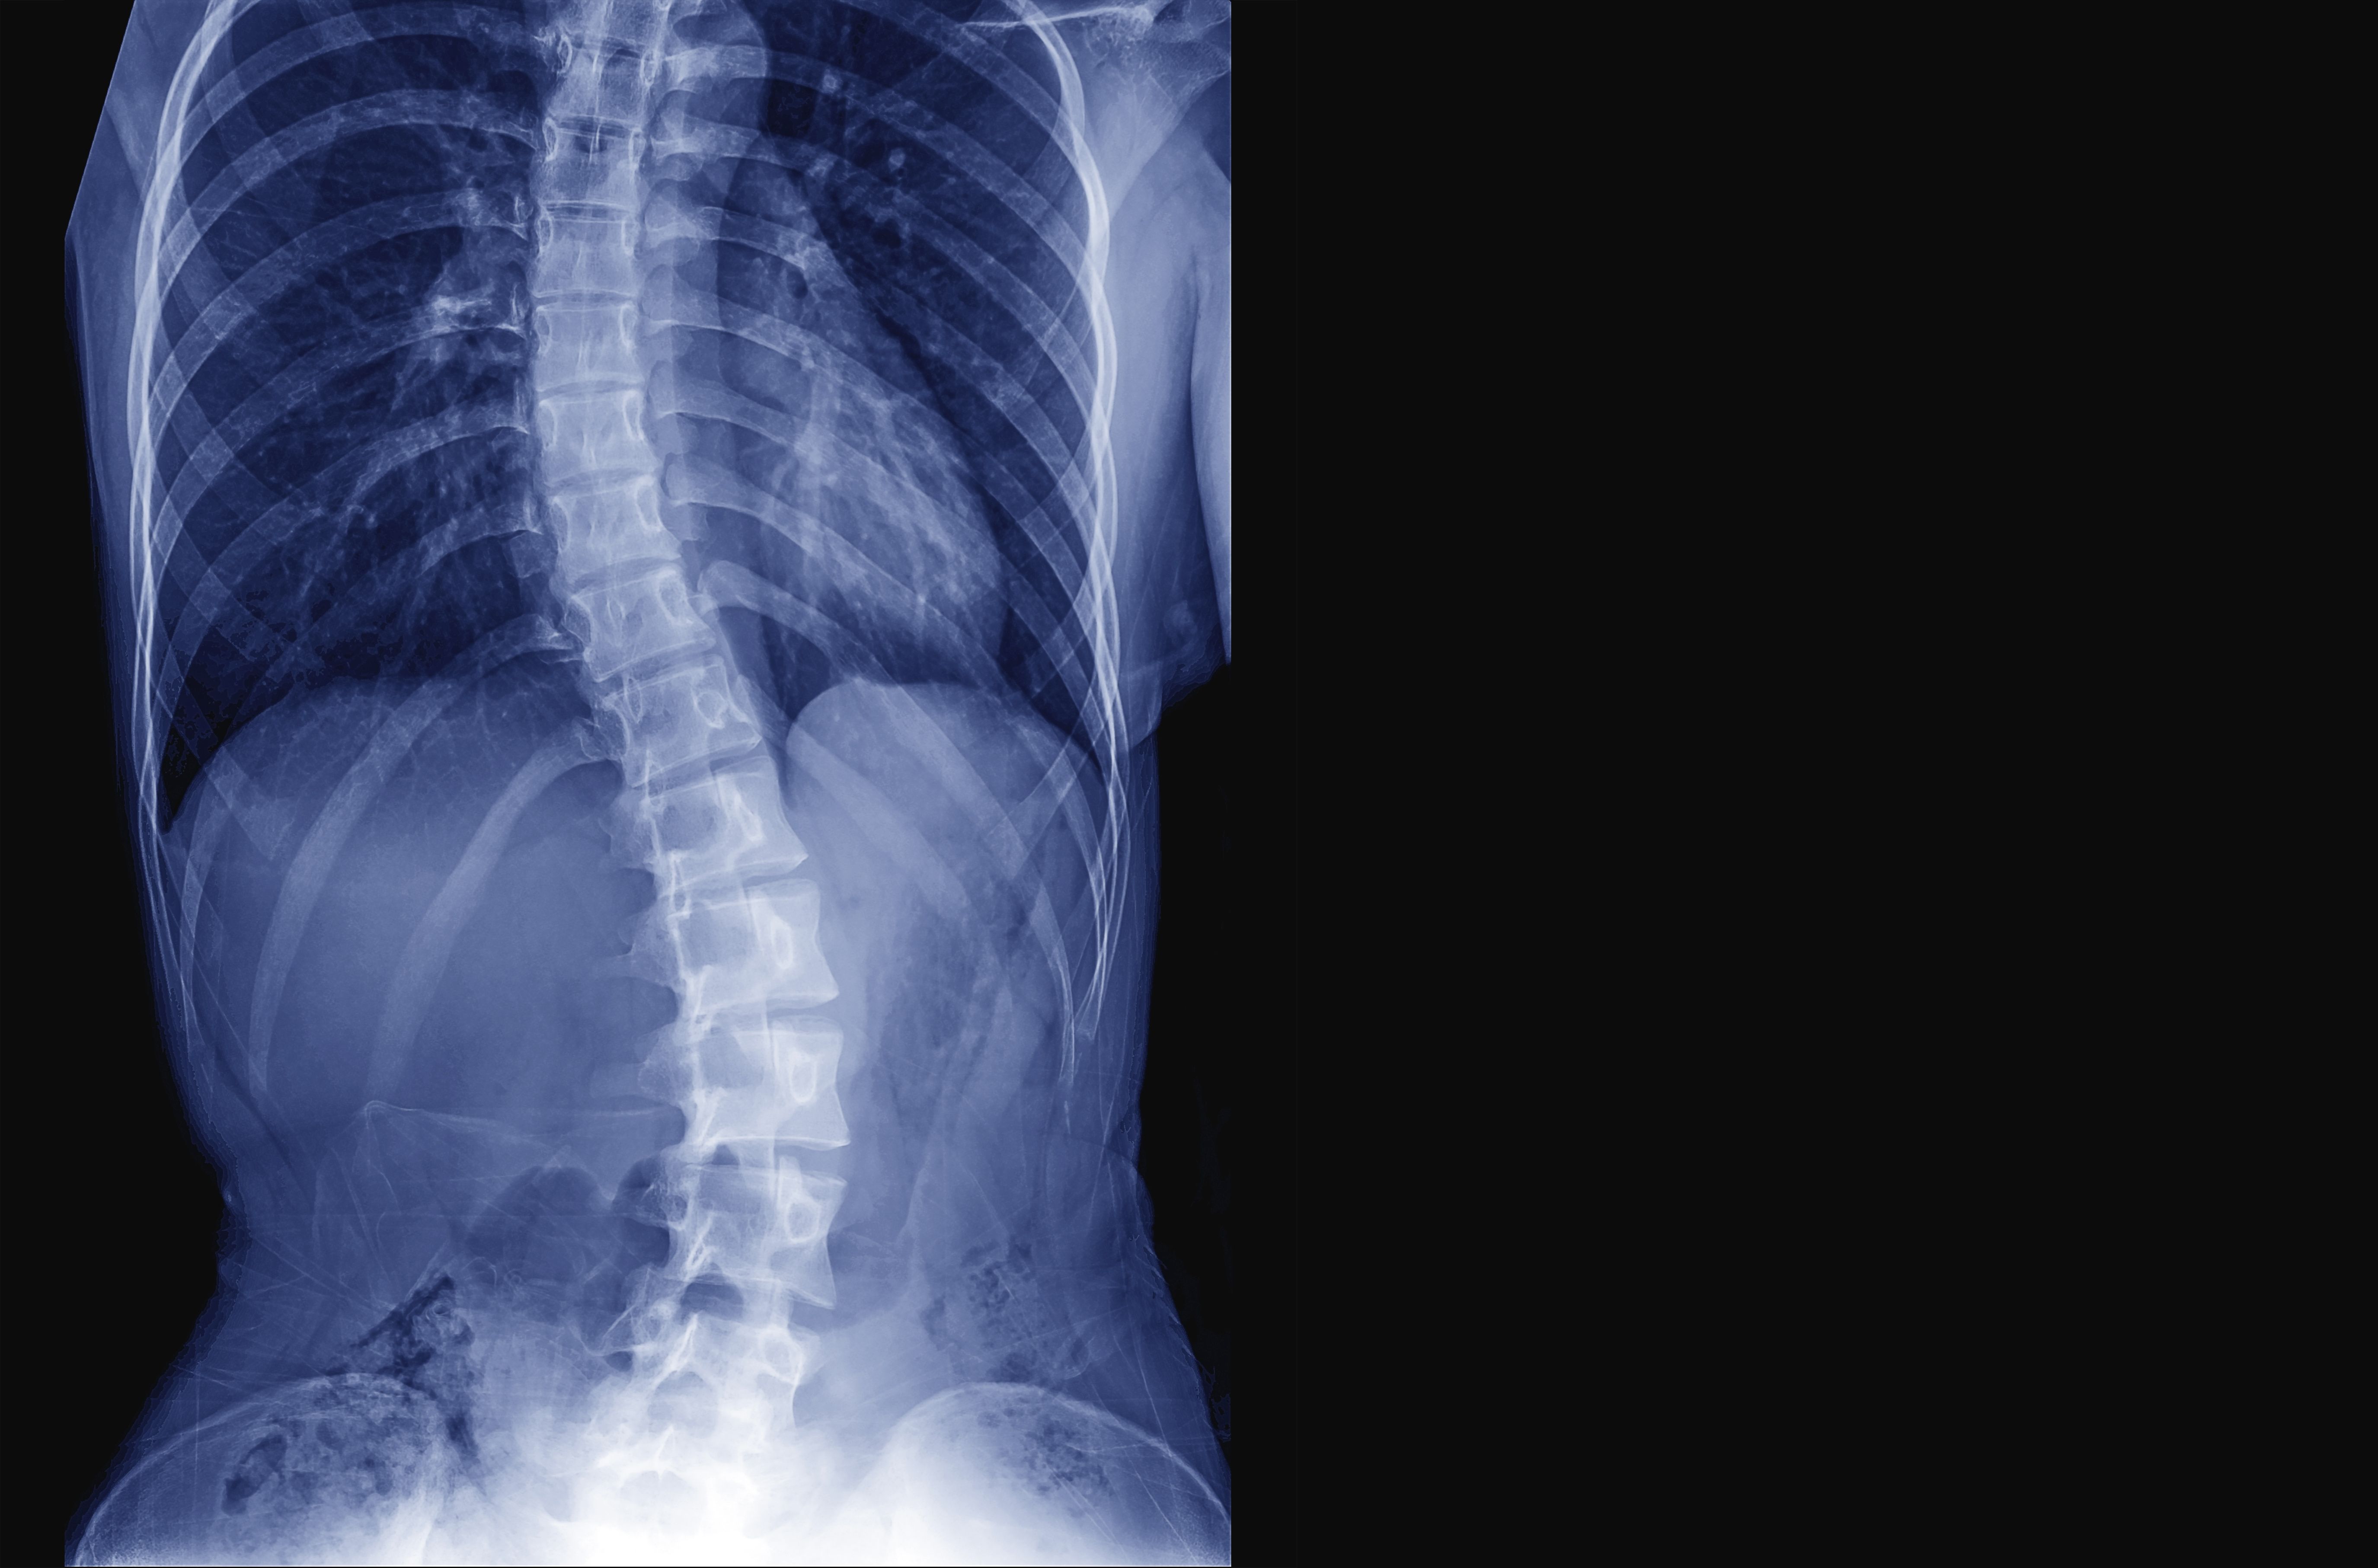

Nonradiographic axial spondyloarthritis

Be aware that changes in geometry, bone mineral density, and micro-structure appear early in the disease course of axSpA.